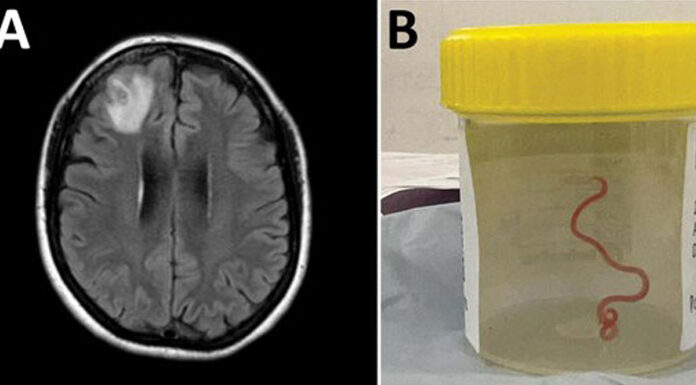

Črv, podoben vrvici, je bil dolg 8 centimetrov, bil je živ in se je zvijal.

"To je osupnilo vse v operacijski dvorani," je povedal Sanjaya...